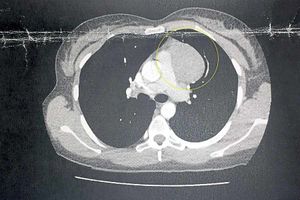

It quickly spread and after being rushed to A&E with back pains, tests revealed she had an 8.5cm mass growing in her chest.

Despite the aggressive nature of Hodgkin lymphoma, it is one of the most easily treated types of cancer and her tumour has now shrunk to 7.5 cm by last month.